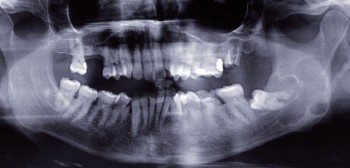

L’OPT est un outil de débrouillage indispensable pour tous les patients.

Sa lecture doit être systématique : état de la denture, structures osseuses environnantes, cavités aériques… Elle a l’avantage d’être bilatérale comparative.

Il faut également toujours comparer le cliché actuel aux clichés antérieurs pour évaluer l’évolution d’une lésion éventuelle de type granulome apical.